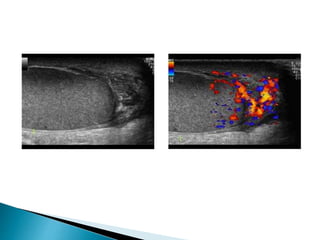

 On ultrasoundvaricoceles are seen as a echo-free serpiginous structures measuring more than 2 mm maximum diameter .  Visible flow may he seen within larger varicoceles.  Their prominence is increased in the upright position and with the Valsalva manoeuvre.

• #40 Ultrasound of varicocele seen as echo-free serpiginous structures.

• #42 Intratesticular varicocele with a tortuous dilatated intra testicular vein with reflux during valsalva